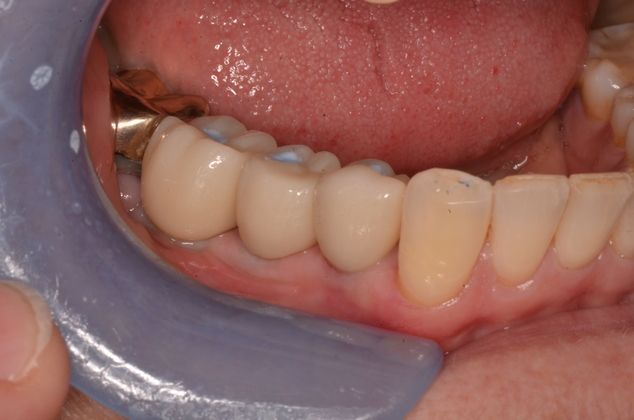

Three missing lower teeth replaced with implants and screw retained crowns.